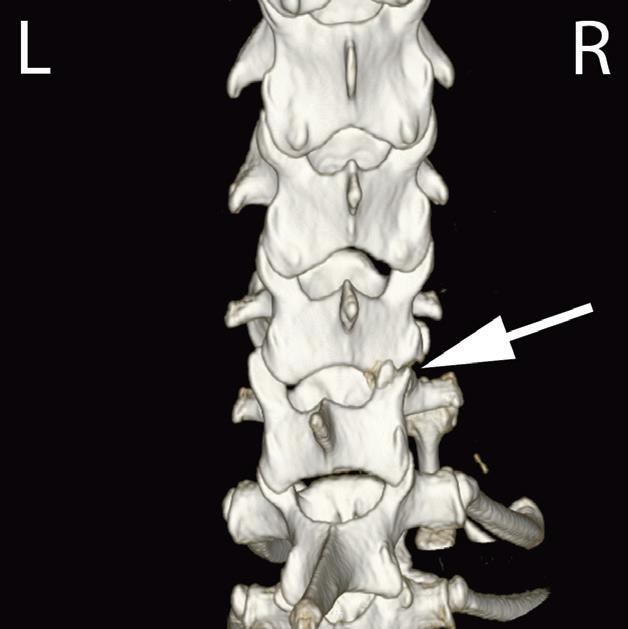

Rycina

3.2.8. Podwichnięcie kręgów szyjnych ze złamaniem wyrostka stawowego (pies) TK i MR

Badania wykonano u 5-letniej samicy mieszańca w typie teriera, która została pogryziona w okolicy szyjnej przez większego psa tego samego dnia, w którym wykonano badania. Podczas wizyty u psa zaobserwowano deficyty neurologiczne z neuroanatomiczną lokalizacją w obrębie C6–T2. Radiogramy przeglądowe ukazały grzbietowe podwichnięcie kręgu C7 względem C6 oraz zwężenie przestrzeni międzykręgowej C6–C7 (a – grot strzałki). Podobne zmiany uwidoczniono na obrazach TK w projekcji strzałkowej i 3D (b, f – grot strzałki). Dodatkowo stwierdzono wieloodłamowe złamanie z przemieszczeniem prawego doczaszkowego wyrostka stawowego kręgu C7 (c–e – strzałka). Dla porównania przedstawiono prawidłowy lewy wyrostek stawowy (f – strzałka). W badaniu MR przestrzeń międzykręgowa C6–C7 była zwężona i wykazywała obniżoną intensywność sygnału w obrazach T2-zależnych (i – strzałka), a przemieszczony materiał dyskowy znajdował się w prawej dobrzusznej części kanału kręgowego (g, h – grot strzałki). W obrazach występują cechy ucisku na rdzeń kręgowy (g–i) oraz zwiększona intensywność sygnału w sekwencji T2-zależnej w obrębie rdzenia na poziomie C6–C7 (h, i), co wskazuje na jego uszkodzenie wewnętrzne. Materiał dyskowy został chirurgicznie usunięty z kanału kręgowego, a podwichnięcie zredukowano i ustabilizowano operacyjnie